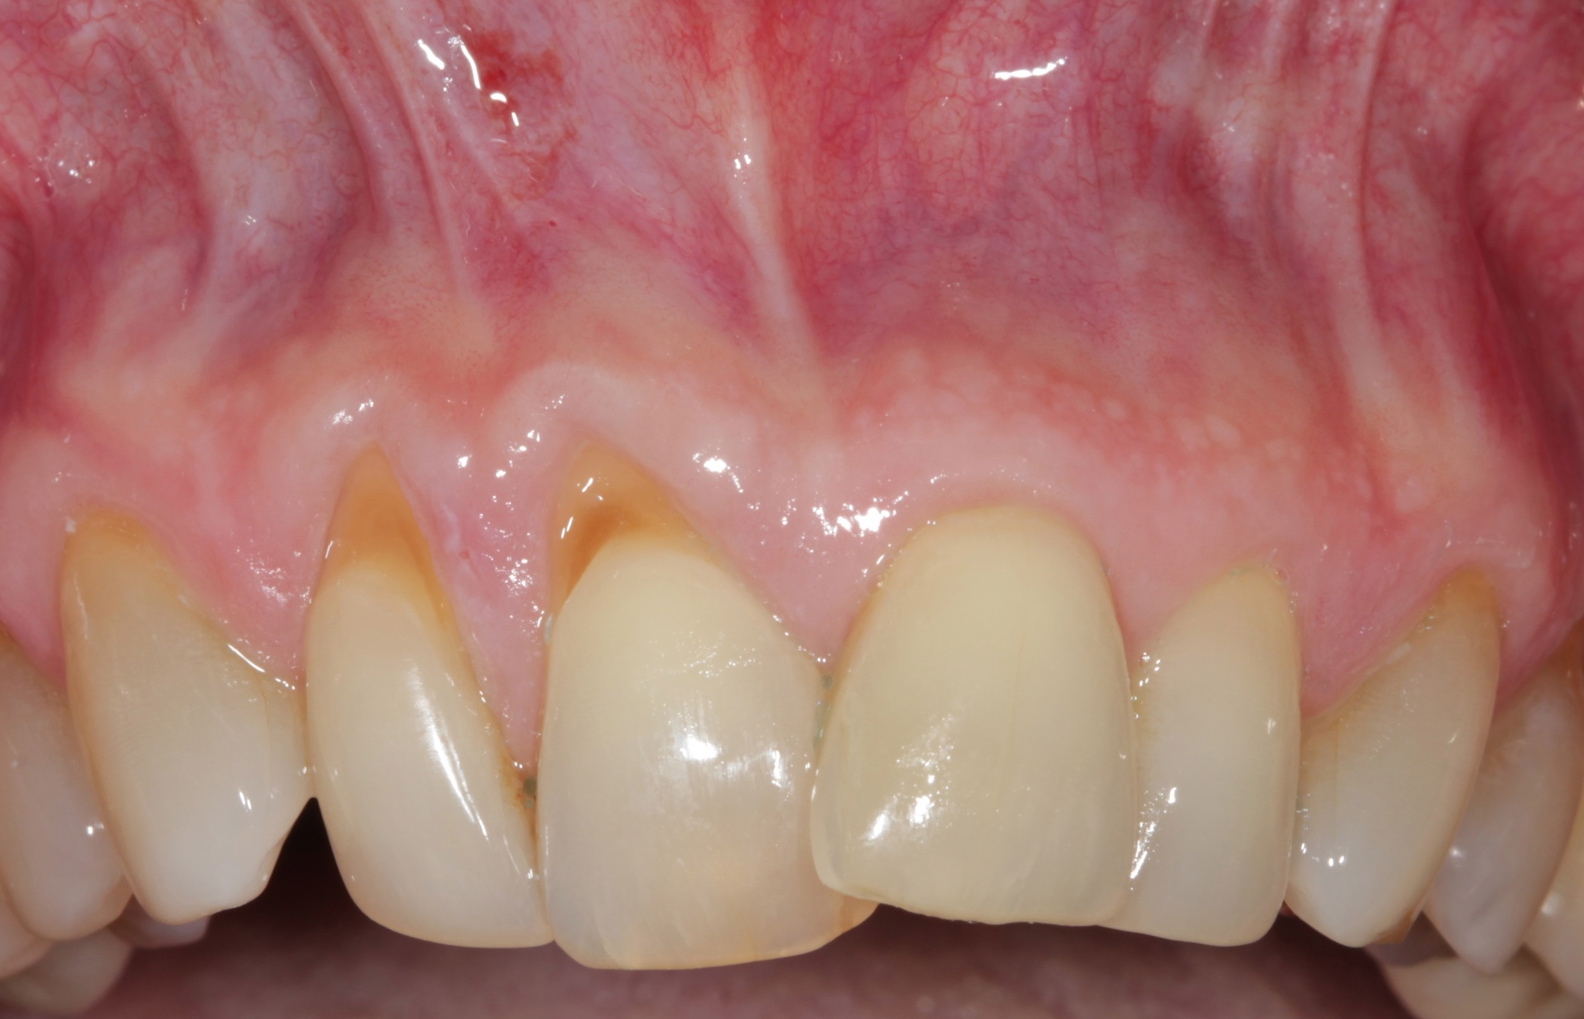

Fig 9. Two years postoperative. A complete root coverage and increase of the zone of attached and keratinized tissue is observed.

Figure 9

Fig 10. Cross-sectional view of the preoperative and postoperative (2 years). A three-dimensional increase of zone of keratinized and attached tissue is observed, restoring the lost attachment apparatus and correcting the gingival deformity in height and width.

Figure 10